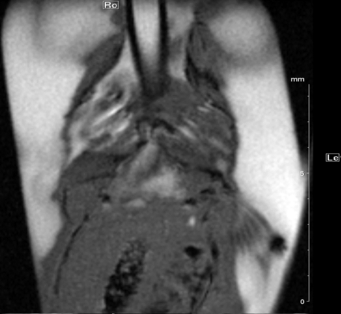

Fig. 3: Newt heart MRI. In the upper panel two localizer scans (RARE method (rapid acquisition with relaxation enhancement) with a repetition time of 2500 ms, echo time of 36.7 ms, slice thickness/interslice distance: 0.50/0.50 mm, field of view 2.50x2.50 cm2 and a matrix of 256/256 (a)) are shown: two 2-chamber views (a,b). In the lower panel an image of the ventricle in axial (c) and coronal (d) orientation is presented. We imaged the animal with an Intragate Flash (Fast Low Angle Shot) sequence: repetition time: 5.6 ms; echo time: 2.9 ms; oversampling: 150 (c) or 300 (d); flip angle: 10 deg; slice thickness/interslice distance: 0.3/0.3 mm; FOV: 15x15 mm and matrix: 256/256 (c) or 128/128 (d) using the 72 mm volume transmit-only room temperature and the cryogenic 4 element 1H array receive-only coil.